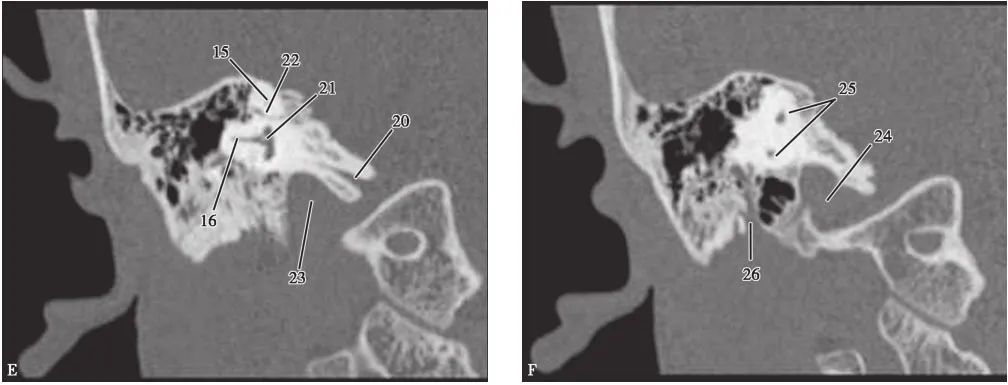

(CT矢状面)

A.耳蜗层面;B.前庭层面;C.面神经管乳突段层面1.颈静脉球;2.内耳道;3.耳蜗;4.前庭导水管;5.后骨半规管;6.总骨脚;7.上骨半规管;8.前庭;9.面神经管迷路段;10.鼓膜张肌;11.圆窗;12.外骨半规管;13.砧骨长脚;14.锤骨颈;15.面神经管乳突段